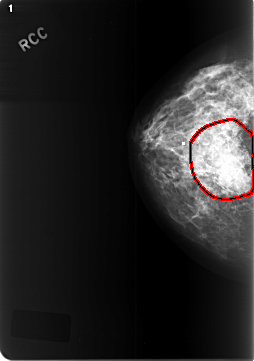

ics_version 1.0 filename C-0471-1 DATE_OF_STUDY 8 9 1997 PATIENT_AGE 48 FILM FILM_TYPE REGULAR DENSITY 2 DATE_DIGITIZED 28 12 1998 DIGITIZER LUMISYS LASER SEQUENCE LEFT_CC LINES 5696 PIXELS_PER_LINE 3520 BITS_PER_PIXEL 12 RESOLUTION 50 NON_OVERLAY LEFT_MLO LINES 5416 PIXELS_PER_LINE 4112 BITS_PER_PIXEL 12 RESOLUTION 50 NON_OVERLAY RIGHT_CC LINES 5768 PIXELS_PER_LINE 4056 BITS_PER_PIXEL 12 RESOLUTION 50 OVERLAY RIGHT_MLO LINES 5936 PIXELS_PER_LINE 4168 BITS_PER_PIXEL 12 RESOLUTION 50 OVERLAY |

FILE: C_0471_1.RIGHT_CC.OVERLAY TOTAL_ABNORMALITIES 1 ABNORMALITY 1 LESION_TYPE MASS SHAPE ASYMMETRIC_BREAST_TISSUE MARGINS ILL_DEFINED ASSESSMENT 5 SUBTLETY 5 PATHOLOGY MALIGNANT TOTAL_OUTLINES 1 BOUNDARY |